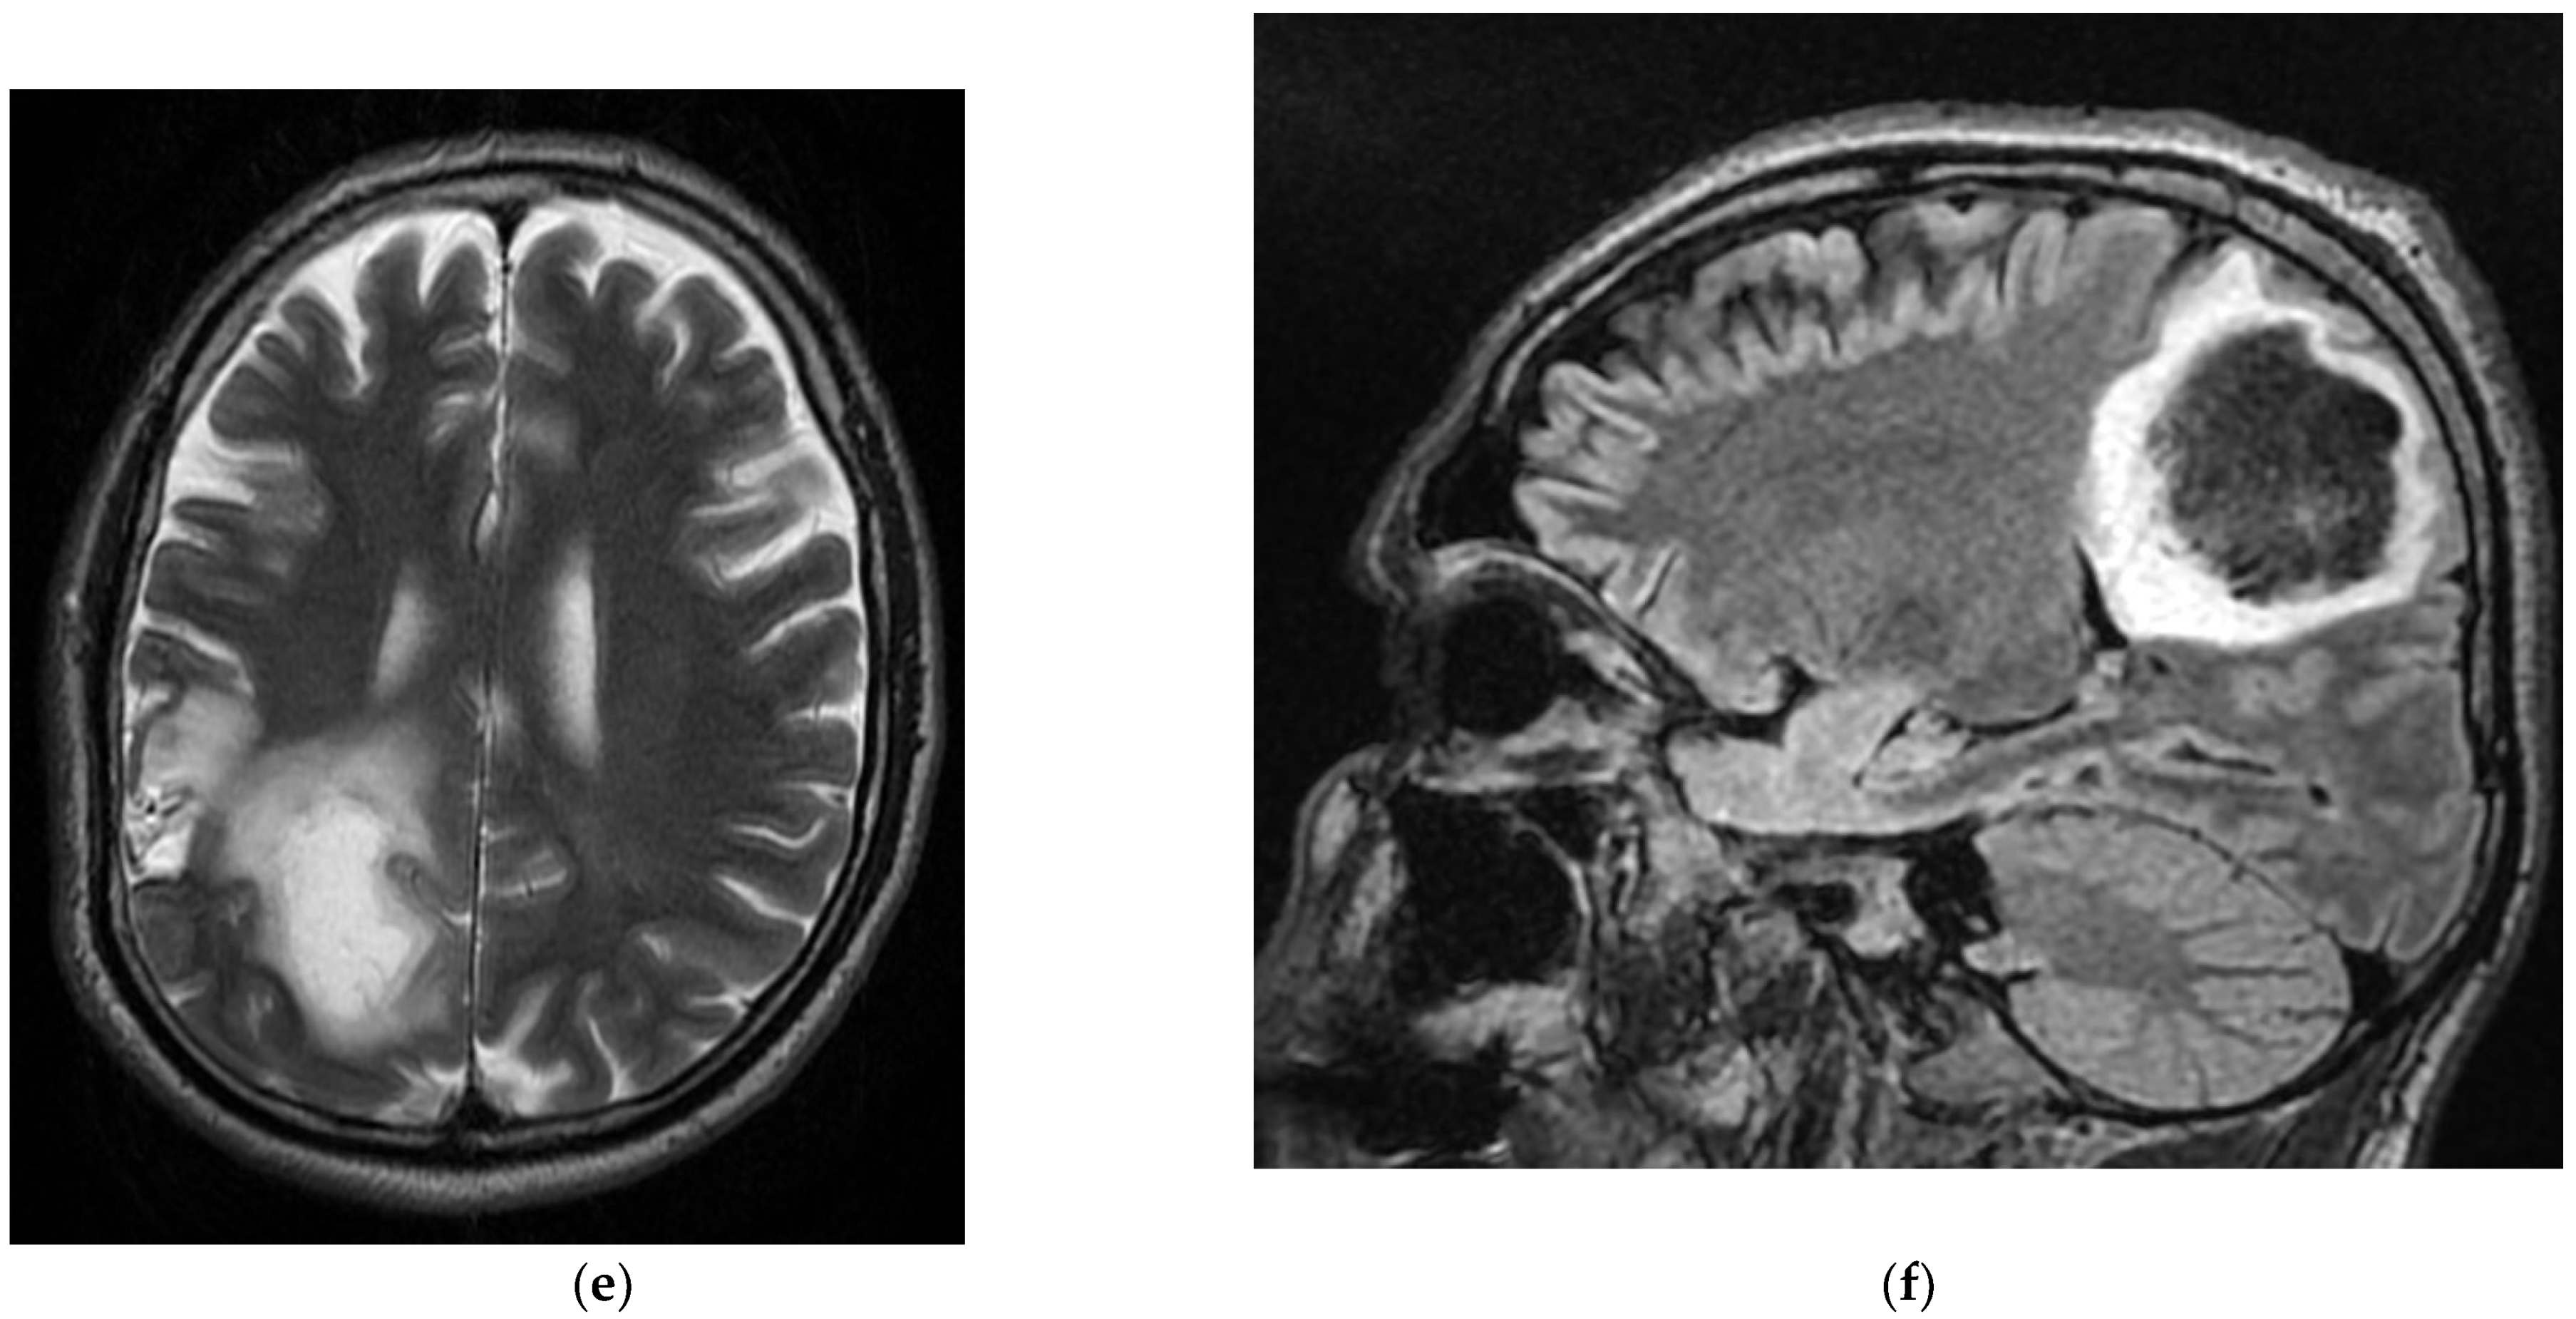

During hospitalization, the patient underwent native and contrast-enhanced abdominal MRI, which revealed a pancreatic cephalic expansive–infiltrative formation with gastroduodenal infiltration and locoregional adenopathy and a simple LDH cyst, and a contrast brain MRI showed a cystic solid mass with peripheral annular gadophilia, axial dimensions of 23/20 mm, extensive perilesional oedema, and a left midfrontal subcortical–left-frontal expansive lesion, most likely of secondary determination significance (Figure 7).

Figure 7. MRI T1 (a), T2 (b), and T1 sequence with contrast injection in the Case 7 patient (c) show solid-cyst mass (a,b) with ring-shaped peripheral gadophilia (c) and extended perilesional edema (b), disposed in the middle-left subcortical area. These pathological images are suggestive of a left-frontal expansive lesion, most likely meaning a secondary determination.